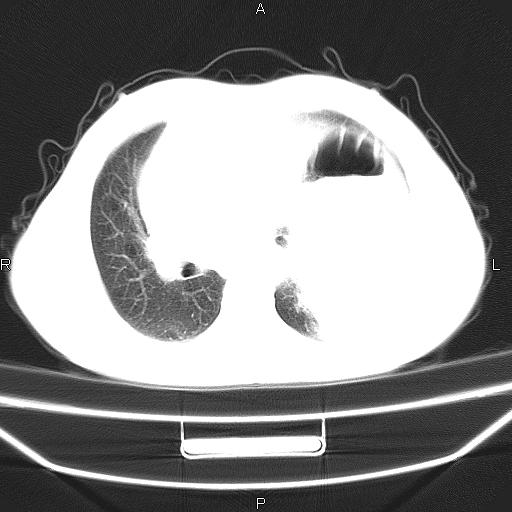

患者,男。50岁。近几日有咳嗽症状,无其他不适,既往病史无,考虑膈疝。请前辈们看看指导指导。

膈膨升,左下肺通气不良,膈肌好像还完整。

考虑左侧膈疝。

左侧膈疝。

符合隔膨升,膈肌较完整。